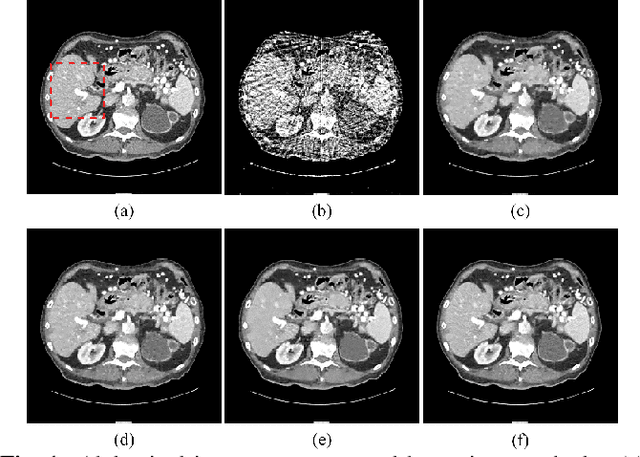

Abstract:Over the past few years, dictionary learning (DL)-based methods have been successfully used in various image reconstruction problems. However, traditional DL-based computed tomography (CT) reconstruction methods are patch-based and ignore the consistency of pixels in overlapped patches. In addition, the features learned by these methods always contain shifted versions of the same features. In recent years, convolutional sparse coding (CSC) has been developed to address these problems. In this paper, inspired by several successful applications of CSC in the field of signal processing, we explore the potential of CSC in sparse-view CT reconstruction. By directly working on the whole image, without the necessity of dividing the image into overlapped patches in DL-based methods, the proposed methods can maintain more details and avoid artifacts caused by patch aggregation. With predetermined filters, an alternating scheme is developed to optimize the objective function. Extensive experiments with simulated and real CT data were performed to validate the effectiveness of the proposed methods. Qualitative and quantitative results demonstrate that the proposed methods achieve better performance than several existing state-of-the-art methods.

Abstract:Traditional dictionary learning based CT reconstruction methods are patch-based and the features learned with these methods often contain shifted versions of the same features. To deal with these problems, the convolutional sparse coding (CSC) has been proposed and introduced into various applications. In this paper, inspired by the successful applications of CSC in the field of signal processing, we propose a novel sparse-view CT reconstruction method based on CSC with gradient regularization on feature maps. By directly working on whole image, which need not to divide the image into overlapped patches like dictionary learning based methods, the proposed method can maintain more details and avoid the artifacts caused by patch aggregation. Experimental results demonstrate that the proposed method has better performance than several existing algorithms in both qualitative and quantitative aspects.